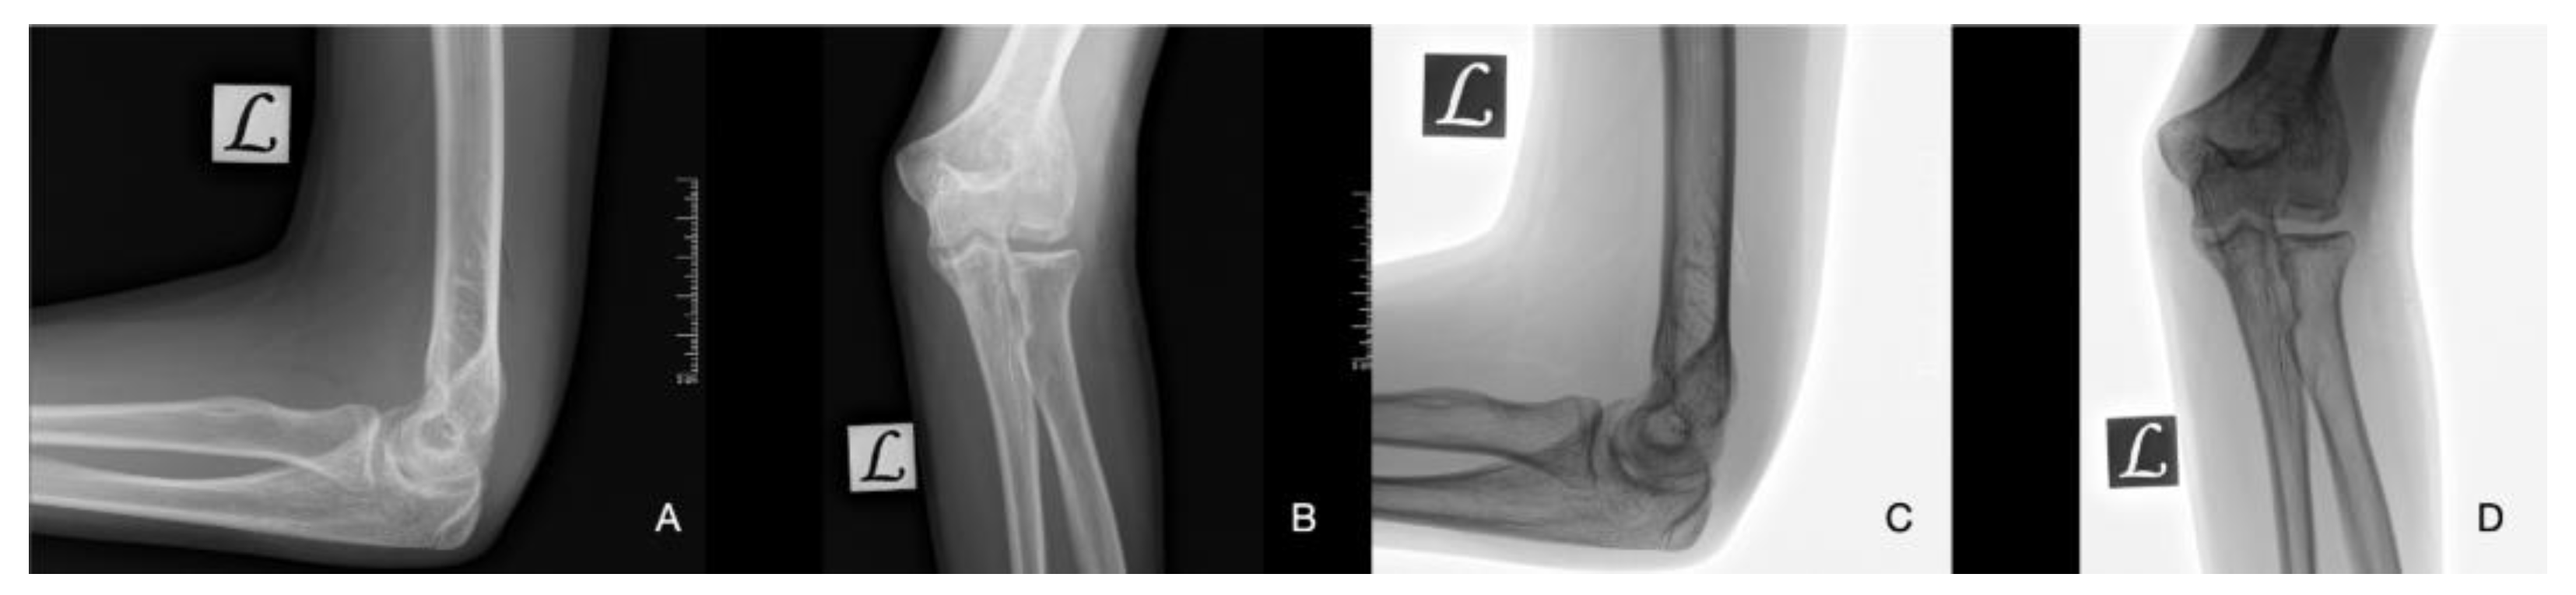

| Stage 1 | Small subchondral compression | Intact Lesion | A stable lesion of the softened area covered by intact cartilage. | Thickening of articular cartilage and low signal changes | Small change of signal, without clear fragment margins. | Epiphyseal cartilage lesion with necrotic center |

| Stage 2 | Partially detached osteochondral fragment | A lesion with signs of early separation | Lesions with partial discontinuity which are stable when probed | Articular cartilage has been breached with a low signal rim behind the fragment indicating fibrous attachment | OSteochondral fragment with clear margins, without fluid in between | Epiphyseal cartilage lesion with complete or incomplete rim calcification |

| Stage 3 | Completely detached, non-displaced | Partially detached lesion | Lesions with complete discontinuity which are not dislocated (Dead in situ) | High signal changes behind the fragment indicate synovial fluid between the fragment and the underlying subchondral bone | Fluid is visible partially between the fragment and bone | Partially or completely ossified lesion |

| Stage 4 | Completely detached and displaced - loose body | Craters with loose bodies (salvageable or non-salvageable) | Empty defect bed with loose or dislocated fragment | Loose body | Fluid surrounds the fragment but it is still in situ | A healed osseous lesion with scar |

| Stage 5 | Scranton and McDermott modification : Subchondral Cyst | - | - | - | The fragment is completely detached and displaced | Unhealed, detached osseous lesion (Sequestrum) |